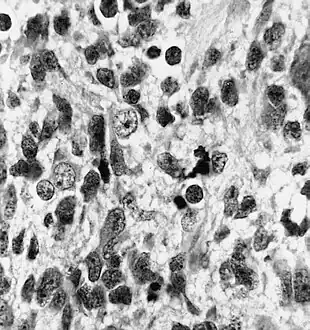

Histologically, medulloepithelioma resemble a primitive neural tube and with neuronal, glial and mesenchymal elements.[8][9] Flexner-Wintersteiner rosettes may also be observed.[10]

Immunohistochemically, neural tube-like structures are vimentin positive in the majority of medulloepitheliomas.[11] Poorly differentiated medulloepitheliomas are vimentin negative.